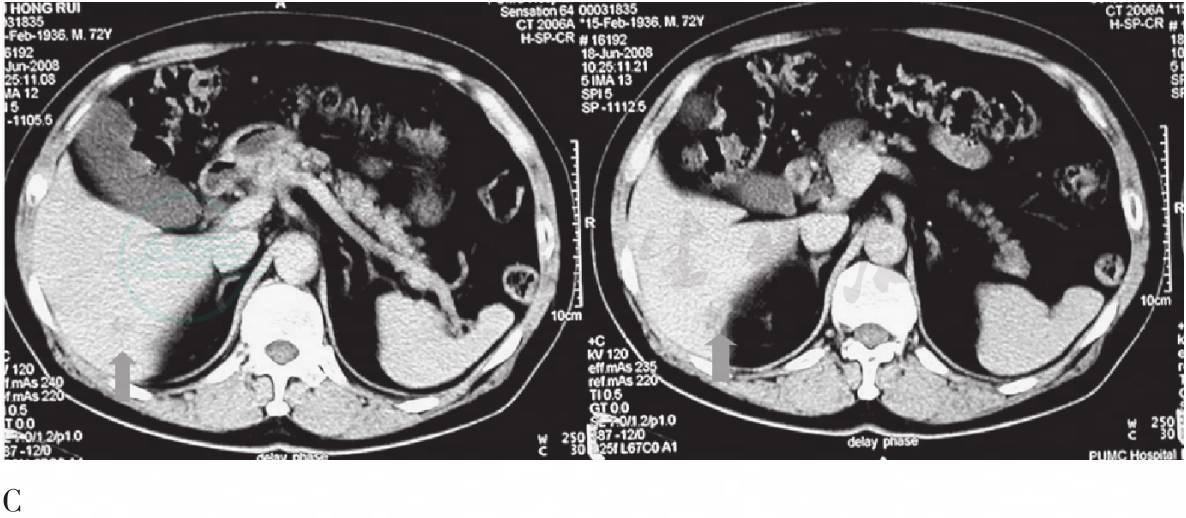

相关检查:肝功能正常,血嗜酸性粒细胞比例略高(6.0%,正常0.5%~5.0%),其余实验室检查无特殊。CT示肝右叶后下缘低密度灶,增强扫描有强化,血池期明显(图1)。

图1 CT腹部横断层图

A. CT平扫,显示肝右叶后下缘不规则低密度灶(箭头);B、C. CT增强扫描血流期及血池期,病灶不同程度强化,血池期更明显